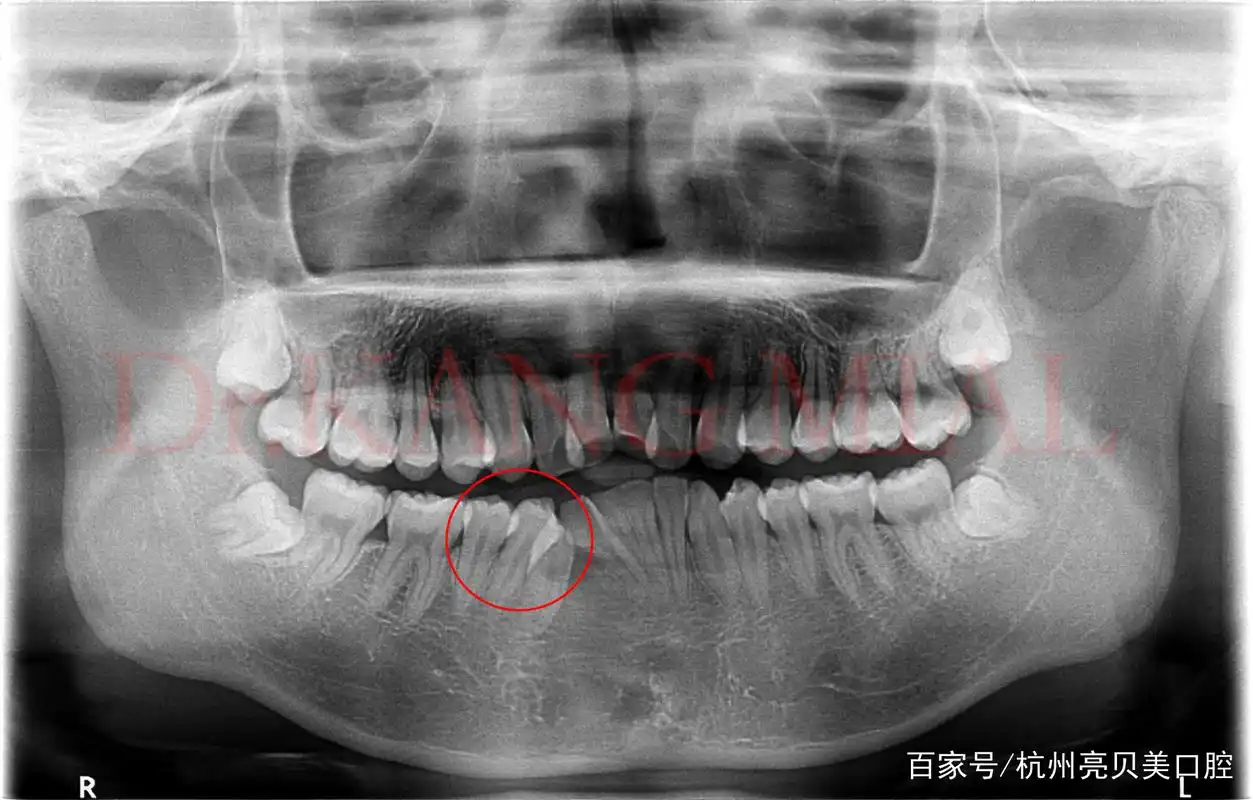

拍牙片丨小编带你解锁看牙新姿势

每个人都有必要去牙科拍牙片检查一下,说不定就有小惊喜

看牙片不求人手把手教你自己看牙片

半夜睡不着刷到这个神奇小组分享一下我的牙片

如何看牙科的x光片?牙片详解,教你看懂牙片!

普通牙片暗藏玄机拔智齿四个小时